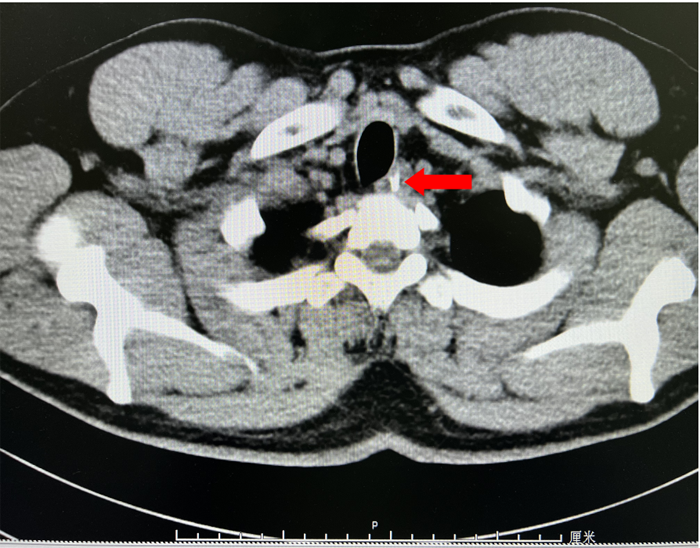

為了解魚(yú)刺與周圍的關(guān)系及是否刺入血管,患者入院后給予完善胸部強(qiáng)化CT,示胸上段管腔內(nèi)高密度影,考慮食管異物。李曙暉主任醫(yī)師結(jié)合患者病史、2次胃鏡結(jié)果及胸部CT等,分析認(rèn)為魚(yú)刺已深深扎入食管壁內(nèi),可行食管黏膜剝離術(shù)暴露出異物后再行取出。12月28日,李曙暉主任醫(yī)師在麻醉和護(hù)理團(tuán)隊(duì)的配合下行胃鏡檢查,內(nèi)鏡下距門齒18cm可見(jiàn)食管黏膜充血水腫,未見(jiàn)異物,遂用黏膜切開(kāi)刀切開(kāi)周圍黏膜及肌層,暴露出異物頂端,再用鱷口鉗鉗住魚(yú)刺頂端,順利取出一枚長(zhǎng)3cm多的魚(yú)刺,看到大部分魚(yú)刺扎入食管壁。術(shù)后對(duì)癥治療后,患者現(xiàn)已痊愈出院。

CT紅色箭頭所示異物